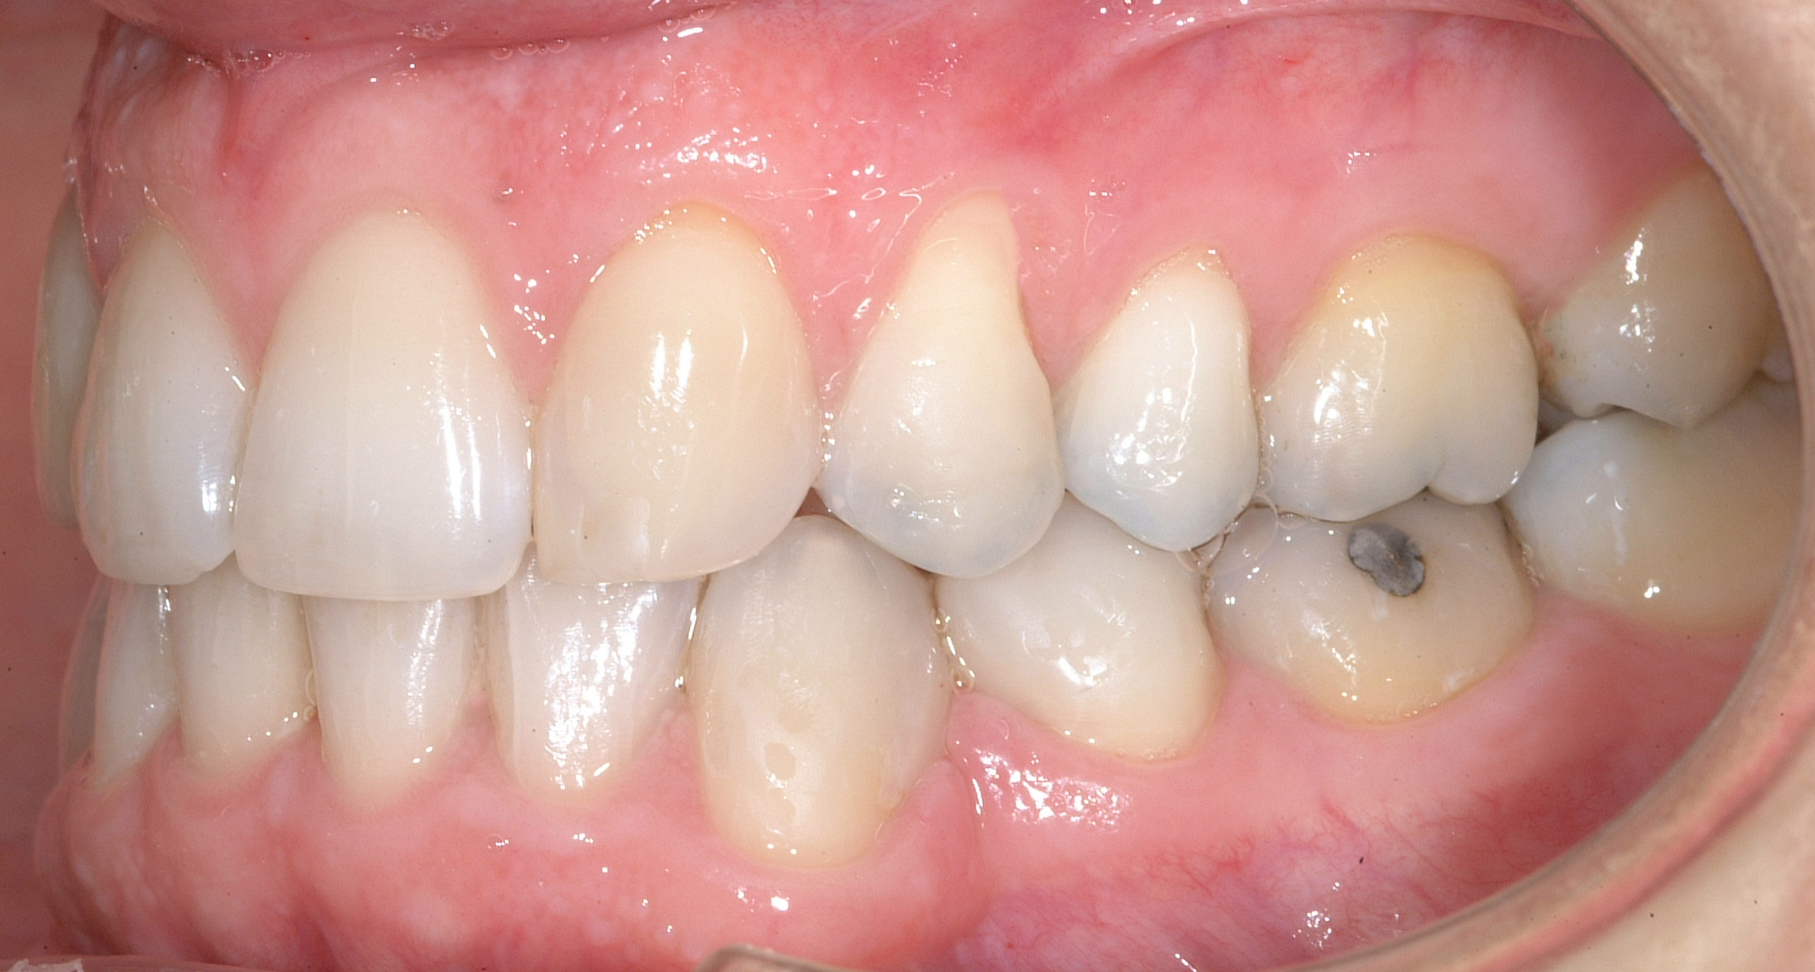

Una paziente di sesso femminile, 38 anni, già trattata ortodonticamente presso altra sede con apparecchiatura fissa a entrambe le arcate in età adolescenziale senza successiva applicazione di alcuna contenzione, si presenta alla nostra attenzione perché insoddisfatta dell’estetica del sorriso; richiede una valutazione per un trattamento ortodontico con apparecchiatura fissa linguale per la presenza di affollamento dentale a entrambe le arcate e difficoltà a mantenere una adeguata igiene orale; si riscontrano agenesia di entrambi gli incisivi laterali superiori (1.2 e 2.2) e del secondo premolare inferiore destro (4.5). Presentiamo la risoluzione del caso mediante trattamento ortodontico estrattivo a entrambe le arcate, eseguito con apparecchiatura linguale invisibile 2D e meccanica asimmetrica e seguito a medio termine da riabilitazione implanto-protesica e contenzione fissa.

La valutazione clinica e gli esami effettuati confermano la presenza di agenesia degli incisivi laterali superiori (1.2 e 2.2) e del secondo premolare inferiore destro (4.5).

L’analisi ortodontica e la valutazione parodontale, con particolare riferimento alla posizione della radice del canino superiore destro (1.3), distoinclinata e trasposta alla radice del primo premolare (1.4) come evidente dalla radiografia panoramica e dalle immagini intraorali, ci hanno guidati nella programmazione di un trattamento estrattivo asimmetrico a entrambe le arcate.